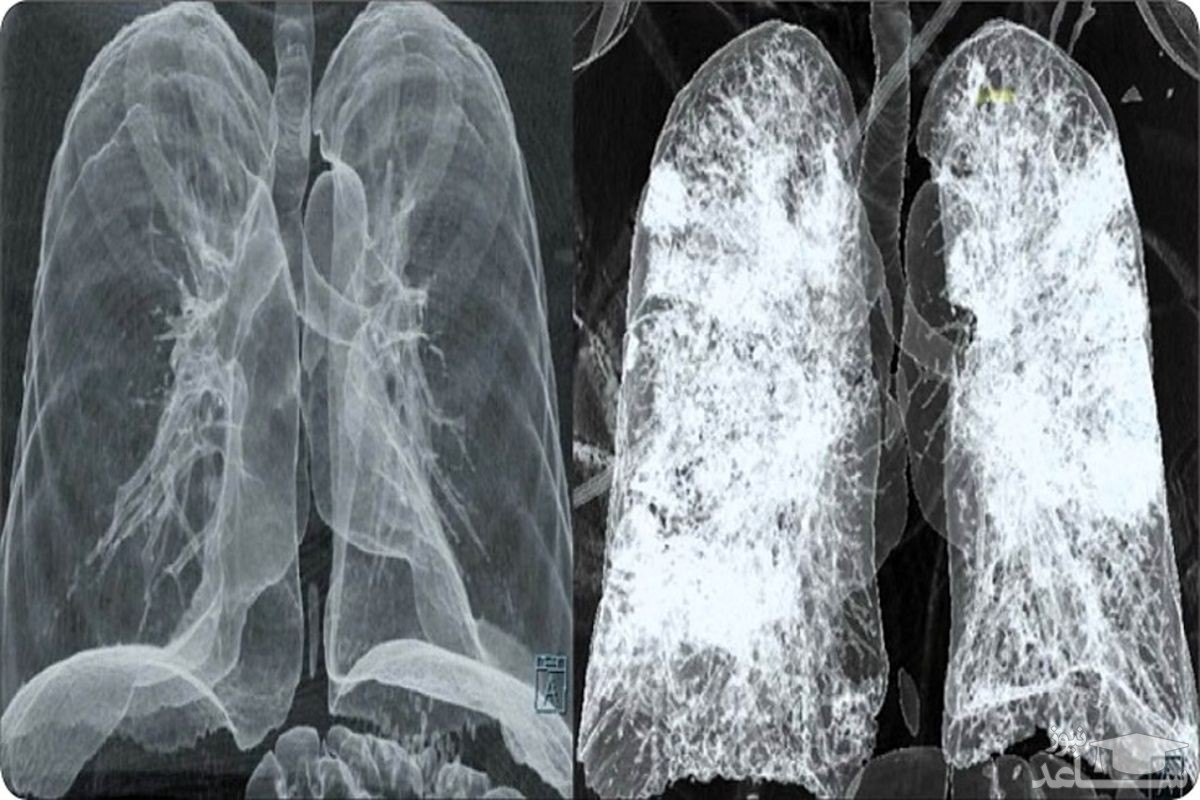

دو تصویر عکس برداری که سازمان سلامت اس اس ام تهیه کرده و هر دو تصویر از افراد مبتلا، اما یکی متعلق به فرد واکسینه شده و دیگری مربوط به فردی است که واکسینه نشده، تفاوت اثر ویروس بر ریه افرادی را نشان می دهد که از لحاظ واکسیناسیون شرایط متفاوتی دارند.